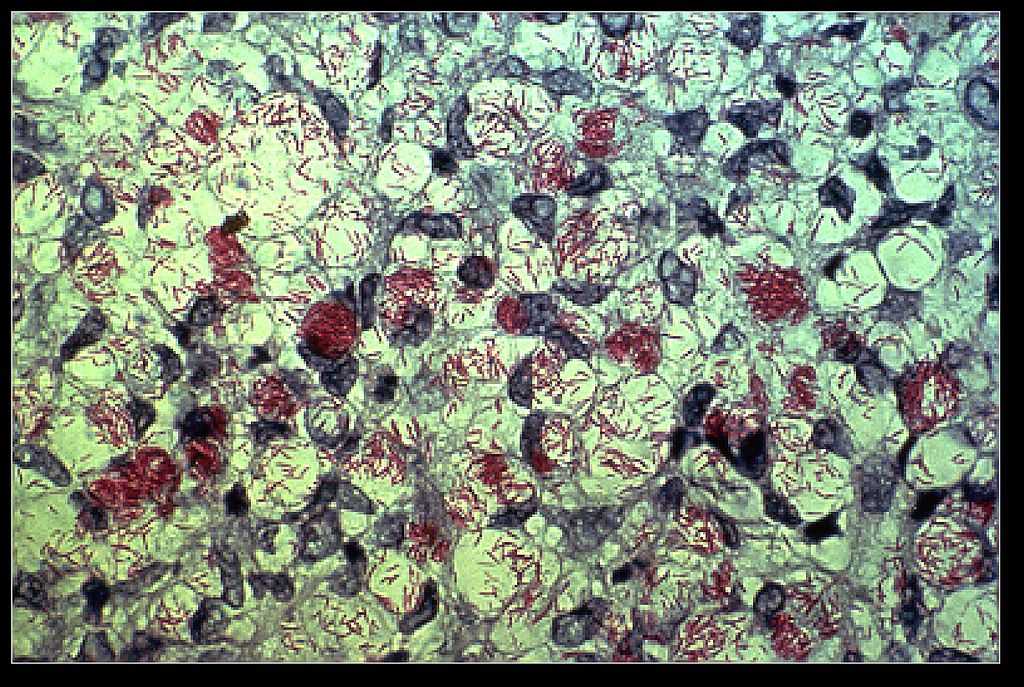

Η νόσος του Hansen ή αλλιώς λέπρα, είναι λοιμώδης νόσος που οφείλεται στο βακτηρίδιο Mycobacterium Leprae. Πρόκειται για μια βραδέως εξελισσόμενη νόσο η οποία μπορεί να προκαλέσει βλάβες στο δέρμα, στους οφθαλμούς και στο νευρικό ιστό.